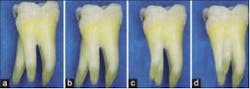

Examples of supernumerary roots. Ribeiro and Consolaro (1997)